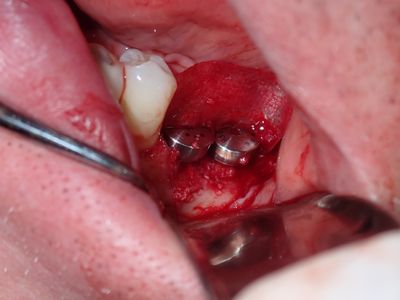

large amount of bone loss at time of exo 36/37 done 2 months ago. Good healing of bone except for small socket area at 36 region. buccal bone lower than palatal about 1mm, decided to place tissue level implants opposed to grafting, gaining back height is unlikely, difficult access case with large tongue. Implants placed with 36 about 1.5mm buccal exposed, 37, .5mm mesial exposed, healing abutments palced grafted all sites with sticky bone followed by collagen membrane soaked in prf fluid, 2 holes cut for implants. additonal fibrin membrance placed on buccal prior to suturing.